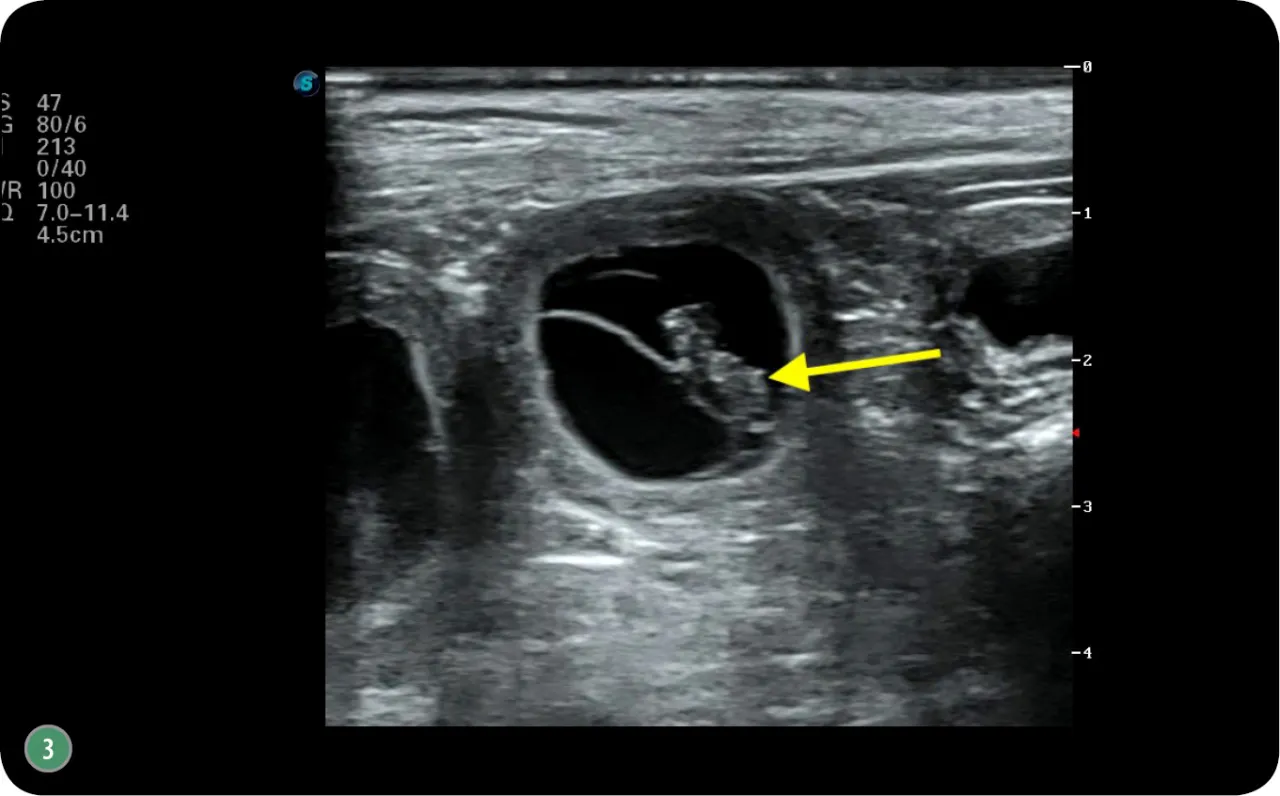

USG: najpewniejsza metoda, by zobaczyć i policzyć przyszłe potomstwo

Moim zdaniem, badanie USG jest najpewniejszą metodą potwierdzenia ciąży. Pozwala ono nie tylko zobaczyć płody, ale także ocenić ich żywotność, obserwując bijące serca. Co więcej, weterynarz może oszacować liczbę kociąt oraz ich wiek ciążowy. USG można wykonać już po 25. dniu ciąży, co daje nam bardzo wczesną i precyzyjną informację.